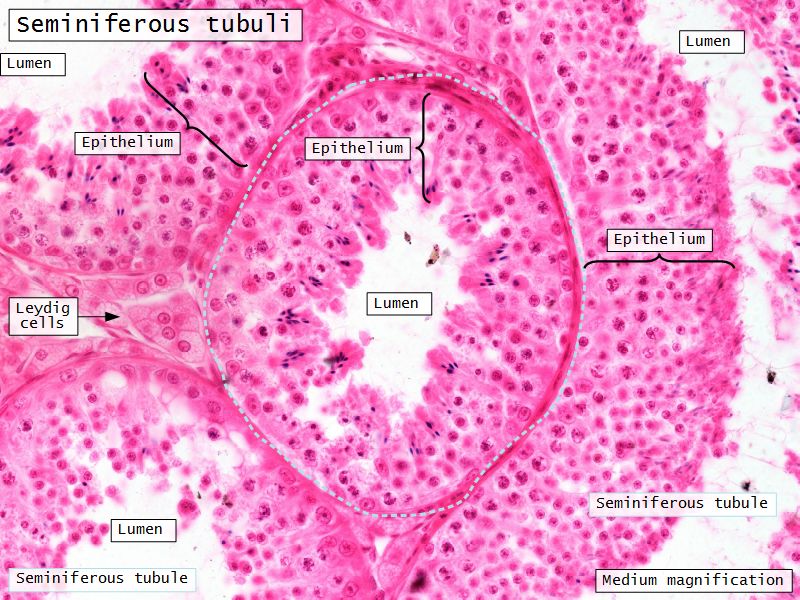

Seminiferous tubuli

- Site of spermatozoa production

- 150 - 250 µm diameter

- Complex stratified epithelium

- Blood-testis barrier

Seminiferous epithelium

- Two types of cells

- Spermatogenic cells

- Sertoli cells

- 4 - 8 cell layers thick

- Forms the blood-testis barrier